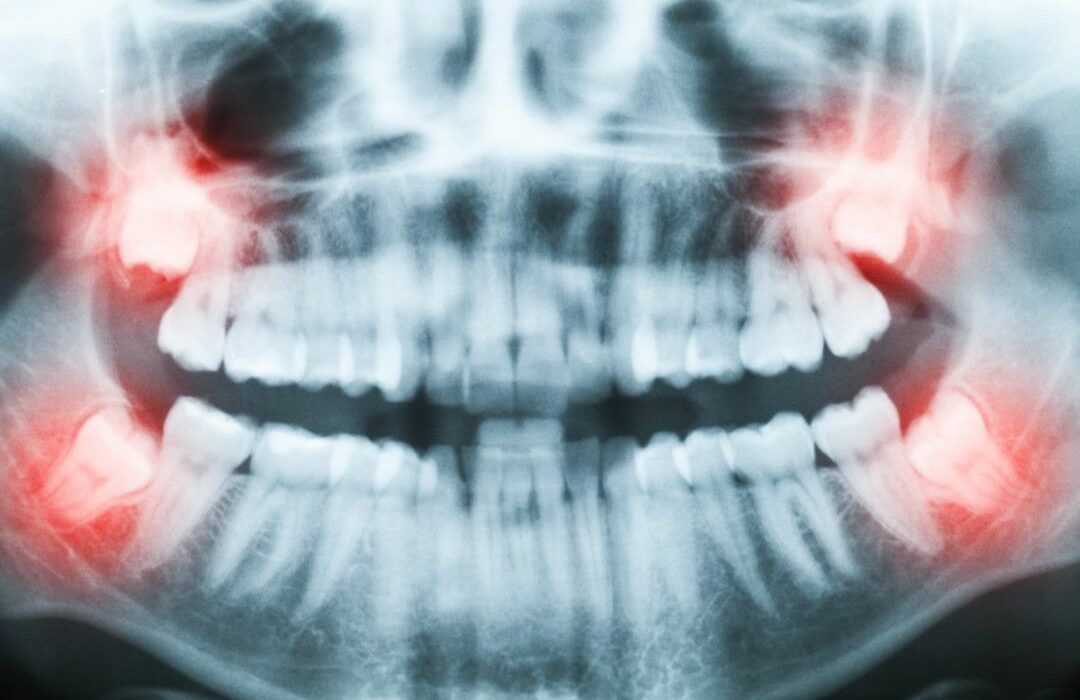

Different Types of Braces

What are the Different Types of Braces? Not everyone’s born with pearly whites, but that doesn’t mean that no one…